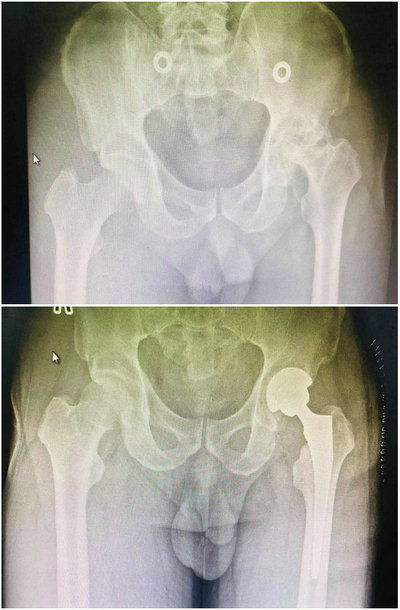

56岁的车先生,大约在7年前出现左髋关节疼痛,当时诊断为左侧股骨头缺血性坏死,由于家庭经济条件较差,迟迟未进行正规手术等治疗,只能口服镇痛类药物缓解症状,但左髋疼痛逐渐加重,左下肢与右下肢对比缩短已超过5cm,左髋关节活动受限明显,基本不能下床行走,十分影响生活,患者及家人都感到生活仿佛蒙上了一层阴影,整日愁眉不展。近年来病人家庭经济条件有所好转,为改善生活质量,寻求手术治疗,经家人及朋友多处打听,来到我院找到骨外科二病区李晓光主任进行规范治疗。

入院后,李晓光主任带领骨外科二病区团队认真分析患者病情,拟行左侧人工全髋关节置换手术,但病人左侧股骨头缺血性坏死7年之久,股骨头塌陷严重,左髋关节骨性关节炎髋臼破坏非常严重,部分髋臼骨质缺损,左髋关节活动度极差,手术难度巨大。考虑到病人既往还有脑梗死病史,入院前仍在口服阿司匹林及氯吡格雷抗凝治疗,需要停用抗凝药物一周,患者平时就患有高血压,血压控制不稳定,所以无法立即进行手术,需要先调理血压,待血压平稳,停用抗凝药物一周以上后再行手术治疗。患者按照医嘱每日口服降压药,骨外科二病区护理团队每天早上都按时给患者测量血压,然后报告给医生,平稳控制血压。除此之外,护士也对患者进行必要的生活护理和心理护理,给患者鼓气树立战胜疾病的信心等。

经过医护团队一周的悉心治疗和护理,在做好了充分的术前准备后,3月20日李晓光主任带领骨外科二病区团队完美地完成了这例复杂的人工全髋关节置换术,手术用时短,术后患者状态很好,无任何不良反应发生,术后双下肢等长,遵医嘱很快开始了康复训练,术后第一日嘱病人行下肢股四头肌自主收缩及踝泵练习,术后第三日辅助病人行左髋关节伸屈活动练习,术后第七日已经能使用助步器进行短距离行走,术后第十一日,不用辅助器具已能独立行走。患者和家属对骨外科二病区医护团队的感激之情溢于言表,不仅脸上洋溢着幸福的笑容,对医生和护士也赞不觉口,对治疗结果更是十分满意,现已康复出院。

术前(上)术后X线检查对比